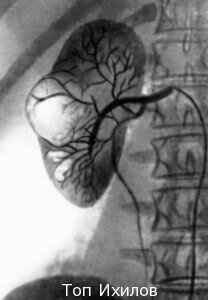

В ходе биопсии почек (kidney biopsy) происходит взятие небольшого фрагмента почечной ткани для дальнейшего исследования под микроскопом с целью обнаружения повреждений или следов заболеваний. В клинике Топ Ихилов эта процедура проходит в соответствии с проверенными годами клинического опыта методиками и с применением самых современных приборов, отслеживающих каждое движение врача и любое изменение в организме.

В большинстве случаев биопсия почек производится с помощью введения через кожу тонкой иглы (чрескожный метод) под контролем визуализирующего оборудования, помогающего направлять иглу и взять пробу. В зависимости от заболевания и индивидуальных особенностей пациента биопсия почки может быть проведена при уретроскопии (при наличии мочекаменной болезни, беременности, трансплантированной почки), либо трансяремным методом (для пациентов с нарушениями свертывания крови и патологиями эндокринной системы).